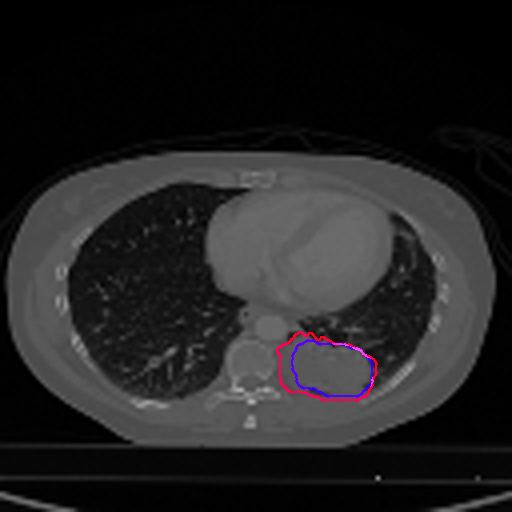

A qualitative analysis of our results reveals the strengths and weaknesses of our proposed model. In most cases, regardless of the size of the ground truth, our model predicts the tumor shapes very well. This is evident from Figure 4 where the ground truth and the prediction (by Deeply Supervised MultiResUNet) are shown in red and blue respectively. Although the tumors are in various arbitrary locations within the lung and appear in diverse sizes, the red and blue margins appear to coincide almost perfectly.

Figure 5 shows a comparison between predictions by the MultiResUNet model and Deeply supervised MultiResUNet model. It can be seen that the latter can delineate the tumor edges more accurately than the former. The ground truth (shown in red) and the prediction (shown in blue) have a more consistent alignment with each other in Deeply Supervised MultiResUNet’s prediction.